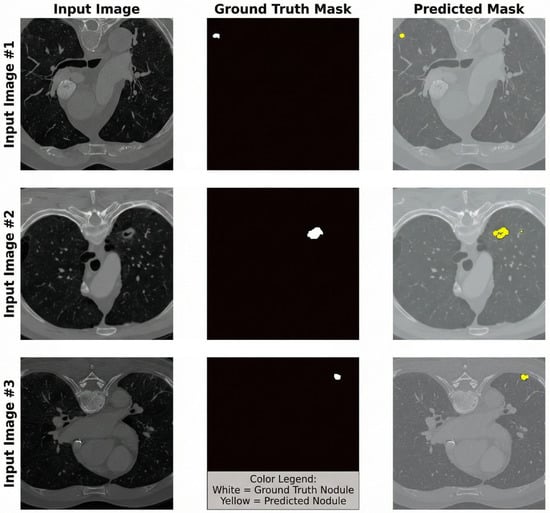

AuraViT-FL: A Resource-Efficient 2D Hybrid Transformer Framework for Federated Lung Tumor Segmentation

by Mohamed A. Abdelhamed, Hana M. Nassef, Sara Abdelnasser, Sahar Selim and Lobna A. Said

Mach. Learn. Knowl. Extr. 2026, 8(2), 34; https://doi.org/10.3390/make8020034 - 3 Feb 2026

Accurate lung tumor segmentation using computed tomography (CT) scans is needed for efficient tumor treatment. However, the development of deep learning models is often constrained by strict patient privacy regulations that limit direct data sharing. This work presents a system that enables multi-institutional [...] Read more.

Accurate lung tumor segmentation using computed tomography (CT) scans is needed for efficient tumor treatment. However, the development of deep learning models is often constrained by strict patient privacy regulations that limit direct data sharing. This work presents a system that enables multi-institutional collaboration while training high-quality lung tumor segmentation models without requiring access to sensitive patient data. The proposed framework features the AuraViT suite, which includes the standard AuraViT—a hybrid model with 136 million parameters that combines a Vision Transformer (ViT) encoder, Atrous Spatial Pyramid Pooling (ASPP), and attention-gated residual connections—and the Lightweight AuraViT (LAURA) family (Small, Tiny, and Mobile). These variants are designed for resource-constrained environments and potential edge deployment scenarios. Training is conducted on publicly available datasets (MSD Lung and NSCLC) in a simulated five-client federated learning setup that emulates collaboration among institutions while ensuring patient privacy. The framework uses a federated learning setup with FedProx, adaptive weighted aggregation, and a dynamic virtual client strategy to handle data and system differences. The framework is further evaluated through ablation studies on model architecture and feature importance. The results show that the standard AuraViT-FL achieves a global mean Dice score of 80.81%, while maintaining performance close to centralized training. Additionally, the LAURA variations show a better trade-off between accuracy and efficiency. Notably, the Mobile variant with ∼5 M parameters reduces model complexity by over 96% while maintaining competitive performance (82.96% Dice on MSD Lung). Full article